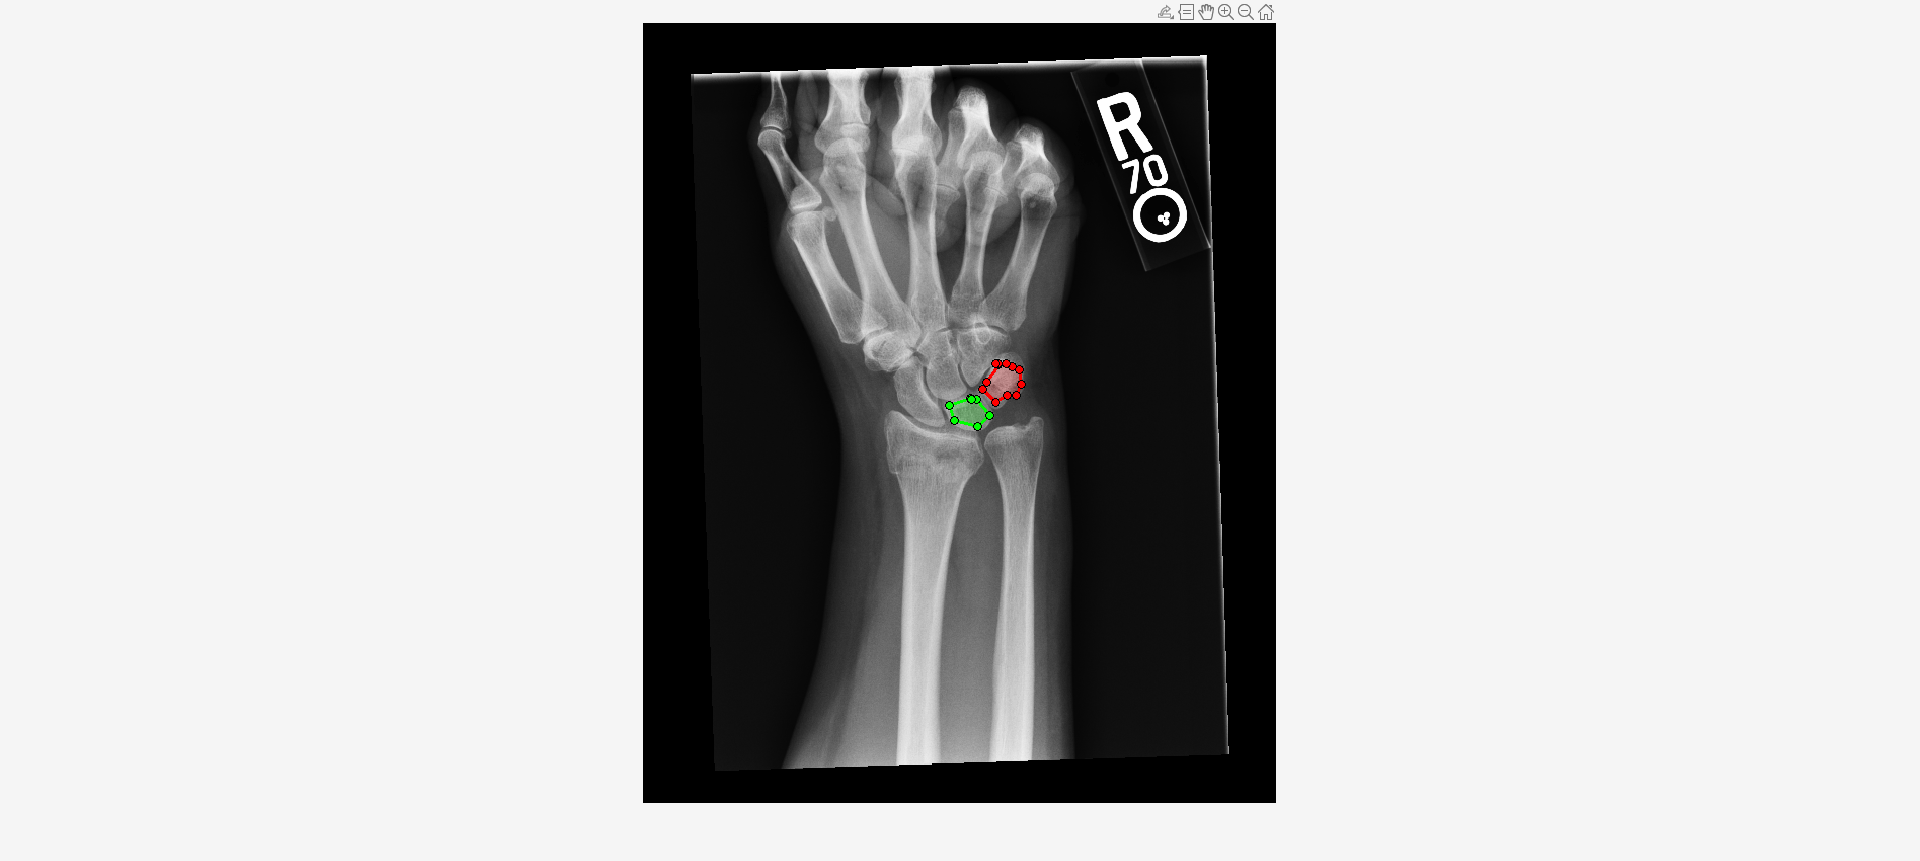

Load an X-ray image into the workspace as a medicalImage object. Visualize the image.

imshow(I,[])Draw two regions of interest (ROI) in the X-ray image. Create masks from the ROIs.

roi1 = drawassisted(Color="g"); roi2 = drawassisted(Color="r");

mask1 = createMask(roi1,I); mask2 = createMask(roi2,I);

Create an ROI label matrix, using different labels for the two ROIs. Create a medicalImage object of the ROI label data.